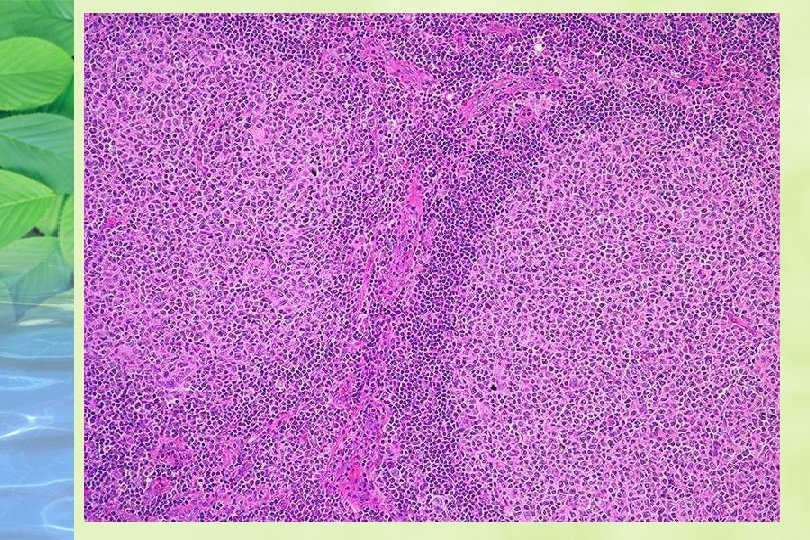

HALLAZGOS HISTOLOGICOS GANGLIO: Arquitectura reemplazada por un patrón difuso o vagamente nodular % pequeño es típicamente nodular Células neoplásicas monótonas , linfocitos pequeños de contorno nuclear irregular, cromatina condensada , nucleolo pequeño, mitosis 19/ 20 hpf

PATRON DE ZONA DEL MANTO Proliferación de células formando manguitos alrededor de centros germinales , obliteración de los sinusoides Infiltración con patrón de zona del manto se a visto en LLC, SLL con diferenciación plasmocitoide, Leucemia prolinfocitica, Linfoma monocitoide de células B, MALT linfomas,